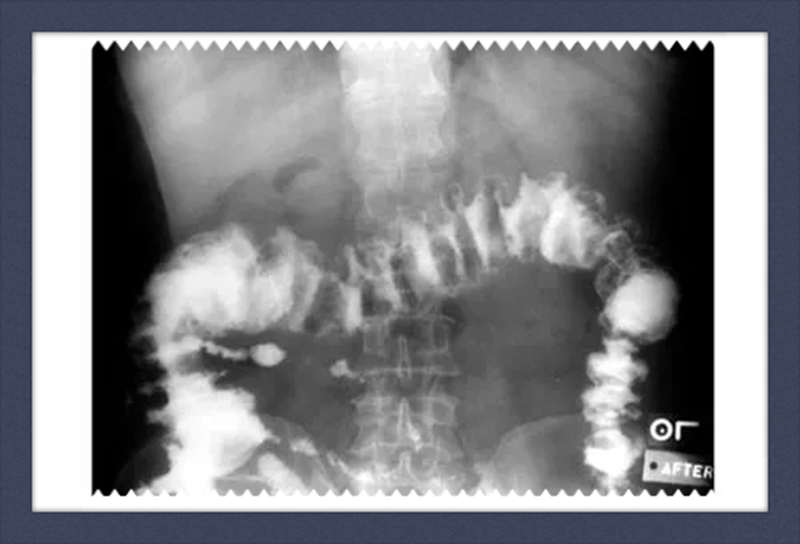

1、影像学检查:如X线胃肠道钡餐造影、CT检查、MRI检查、经直肠超声检查。腹部X线检查适用于伴发急性肠梗阻病人,可见梗阻部位上方的结肠有充气胀大现象。直肠癌术前行直肠MRI为常规检查项目,是术前分期的重要依据。

钡灌肠影像